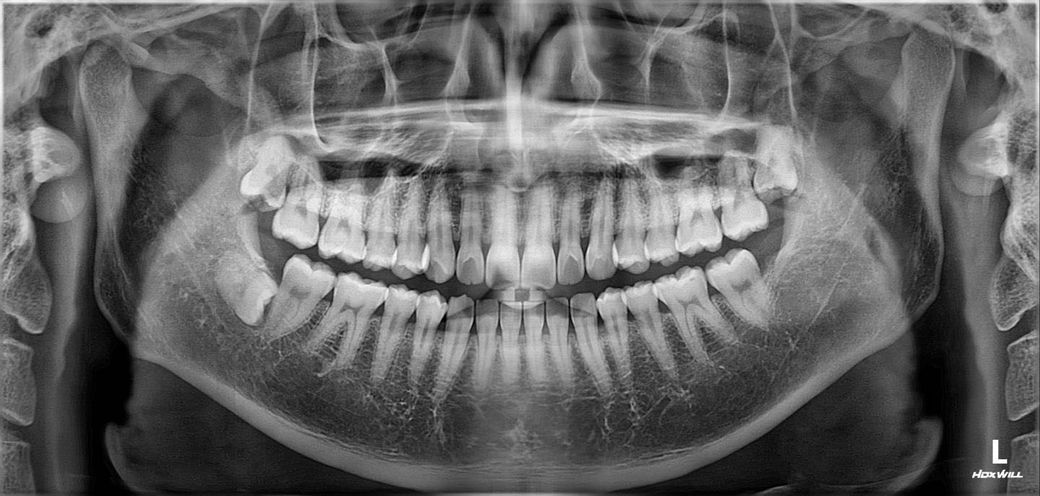

충치 x-ray 촬영사진 (치근단 촬영 포함) 봐주세요

• 1번 째 사진

치아 사이에 인접면충치가 있는것으로 보입니다.

인접면에 충치가 있는 경우에는 일반적으로 보철치료를 하는경우가 많습니다.

충치를 제거했을 경우 신경이 노출이 된다면 신경치료의 가능성이 있습니다.

자세한 확인을 위해서 병원에서 진료를 받아보는 것을 권유드립니다.